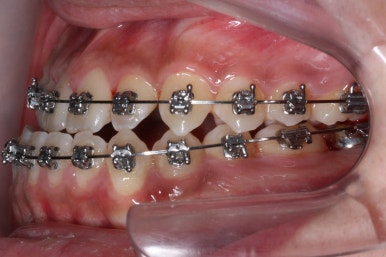

점점 수술전 교정이 진행되는 모습입니다.

각각의 위턱과 아래턱뼈 제위치에 맞게 윗니는 뒤로, 아랫니는 앞으로 내어주게 됩니다. 수술직전까지는 어떻게 보면 교합은 점점 나빠진다고 볼 수 있씁니다.

이 과정에서 힘들어 하시는 분들이 많으신데요. 점점 교합이 서로 멀어질수록 수술은 예쁘게 잘 된답니다.